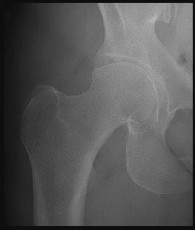

A 38-year-old male presents with right hip pain. He has a history of long-term corticosteroid use for severe asthma. Radiographs demonstrate an area of sclerosis and subchondral radiolucency (crescent sign) in the anterosuperior aspect of the femoral head, consistent with osteonecrosis. According to the modified Ficat and Arlet classification, the presence of a structural subchondral collapse (crescent sign) without narrowing of the hip joint space places him in which stage?

Explanation

The Ficat and Arlet classification is classically used to stage osteonecrosis of the femoral head based on standard radiographs. Stage I has normal radiographs (but positive MRI). Stage II shows cystic/sclerotic changes without subchondral collapse. Stage III is defined by subchondral collapse, which is classically visualized as the 'crescent sign' (subchondral radiolucency indicating mechanical failure of the trabecular bone), but the joint space remains preserved. Stage IV involves secondary osteoarthritis with joint space narrowing and acetabular changes.